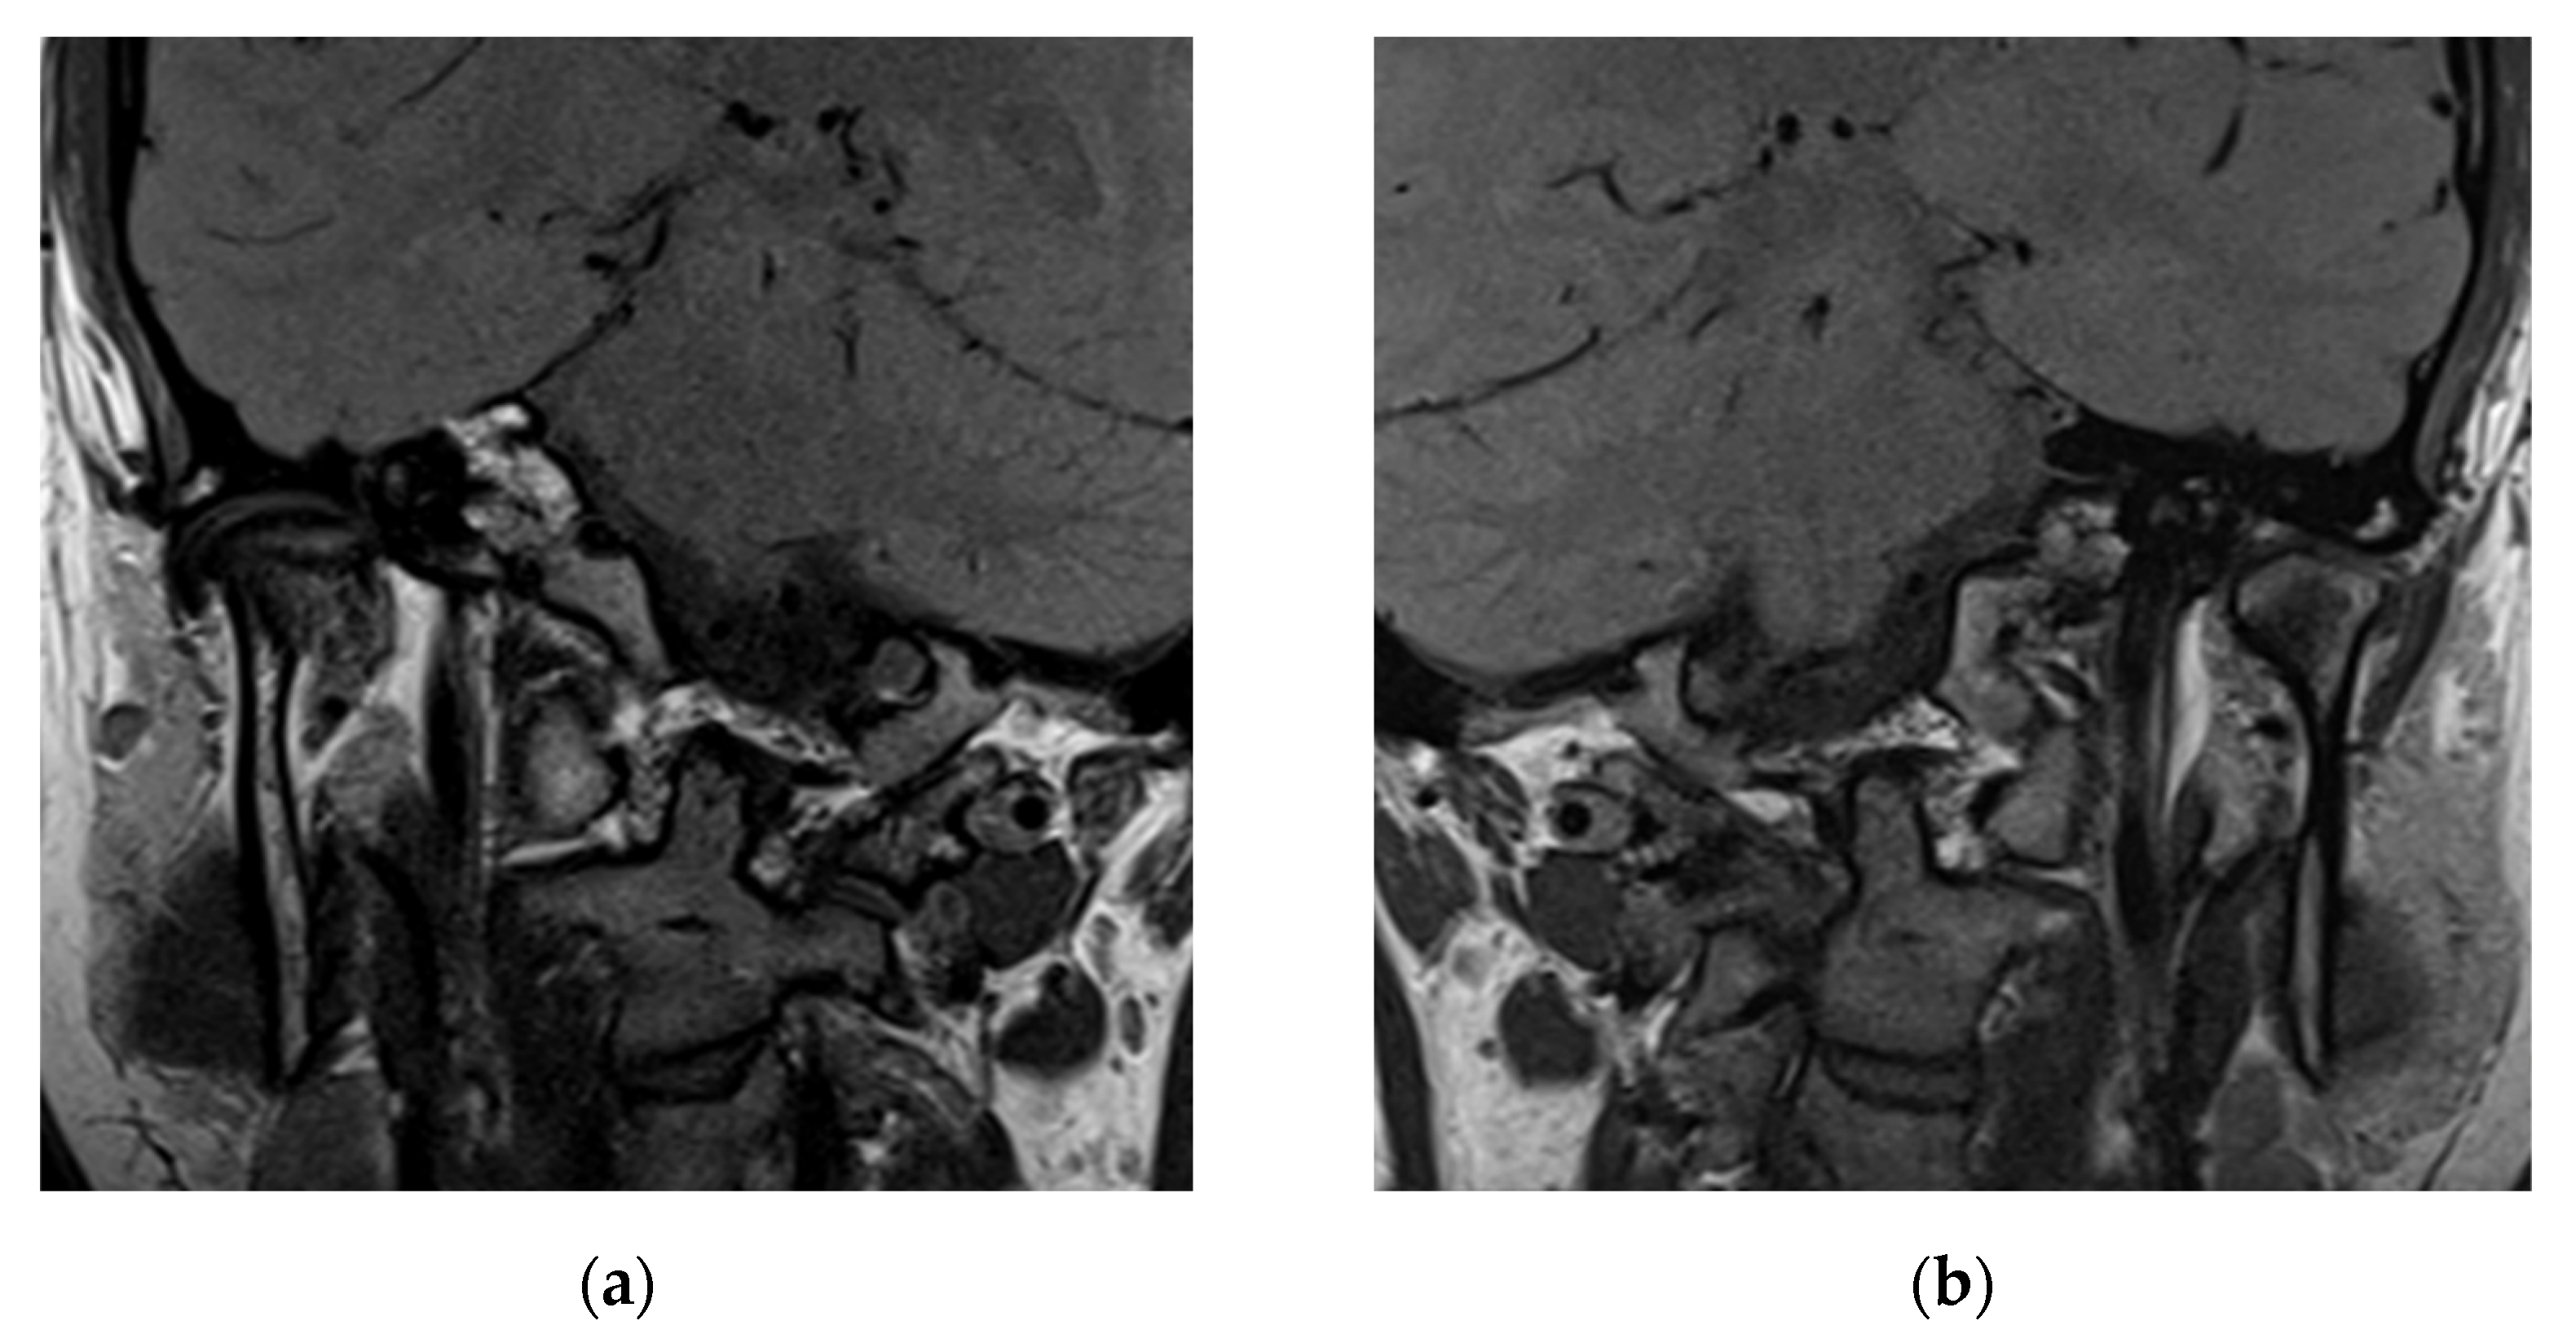

3.3. Case Report